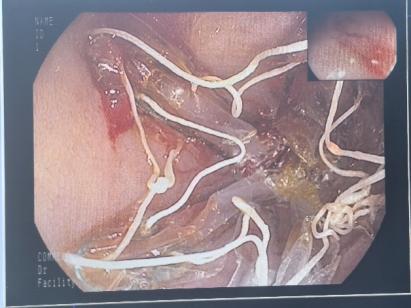

接诊后,胃肠及肝胆外科副主任王若谷详细为杨女士介绍了各种减重方式。经过综合评估,杨女士对胃转流支架治疗比较感兴趣。王若谷详细介绍了该技术的相关情况:胃转流支架是一种新兴的微创减重技术,通过在胃肠道内放置支架,改变食物的消化和吸收路径,从而达到减重的效果。听完介绍后,杨女士决定尝试这种新的治疗方法。

王若谷与内分泌与老年病科、营养科等科室专家,为杨女士制定了个性化治疗方案,提供全方位的治疗支持。入院第2天,王若谷带领团队在麻醉手术科、消化内镜中心等多科室协作下成功完成胃镜下胃转流支架植入,整个过程耗时不到半小时,术后杨女士无明显不良反应,术后第二天顺利出院。

胃转流支架手术是一种先进的微创介入技术,主要用于治疗肥胖症及相关代谢性疾病。通过内镜将一枚“记忆合金支架”精准植入十二指肠起始段,如同在消化道上游架起一座“临时立交桥”,使食物绕过十二指肠和部分空肠,直接进入中段肠道。这一过程可减少营养吸收、调节肠道激素,实现“减重+控糖”。